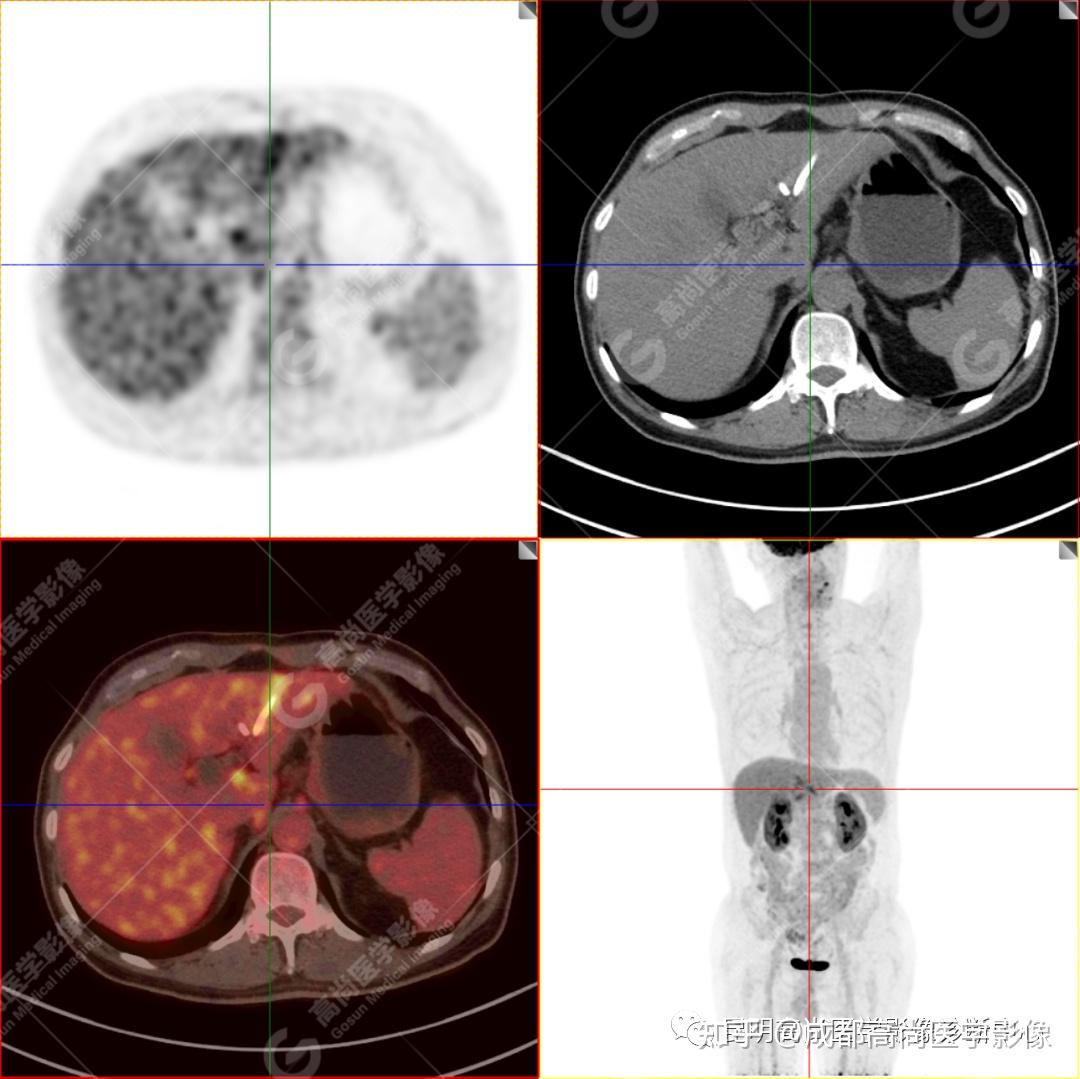

【高尚病例】壶腹周围癌——十二指肠乳头癌一例 - 知乎 By